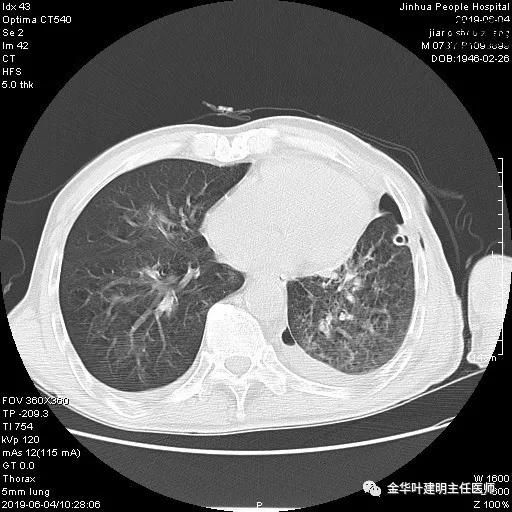

6.4上午:24小时引流出血性乳糜液1800毫升。是否再次手术进行右进胸胸导管结扎,抑或继续保守治疗非常纠结!压力非常大!!多方讨论会诊无法取得一致意见,但一般认为,引流量在1000毫升以上宜积极手术。情况与浙二医院范军强教授联系,请求指导,范教授认为左侧肺手术,损伤胸导管主干的机会较小,多数可保守治疗而愈。在他们的病例中,也有结扎胸导管后引流量仍无减少,效果并不能完全保证。建议可以考虑胸管夹管视察(因为淋巴管压力低,予以适当的压力,漏出量可能会明显减少),同时继续禁食,并静脉营养支持,引流管口可能会有渗液,关注更换敷料。与家属充分沟通后决定试夹管;这天血色素9.0 g/L;胸部CT复查示: